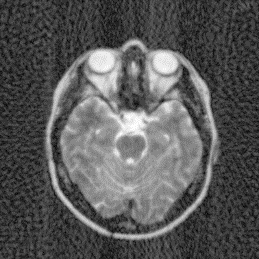

Where x is denoted as the MRI to be reconstructed, y are the k-space data, and Fusubscript𝐹𝑢{F_{u}} represents the under-sampled Fourier encoding matrix. The first term Fuxy22superscriptsubscriptnormsubscript𝐹𝑢xy22{\|{F_{u}}\emph{x}-\emph{y}\|}_{2}^{2} indicates data fidelity that can ensure the consistence between the Fourier coefficients of the reconstructed image and measured data. The second term Risubscript𝑅𝑖{R_{i}} is an analytical, sparsifying transform term, and αisubscript𝛼𝑖{\alpha_{i}} is a factor for balancing data fidelity and transform terms. MR images can be generated by inverse Fourier transform of the sampled k-space data, which are the Fourier coefficient of an object. However, aliasing artifacts (noise-like) are produced by the incoherence of under-sampled k-space in transform domain, as shown in Fig. 1.

Figure 1: The zero-filled reconstruction. (a) is a full-sampled MRI, (b) is a 20% radial sampling mask, (c) is the zero-filled reconstruction under (b), and (d) is the reconstruction using our method. Note that aliasing artifacts are clearly seen in the zero-filled reconstruction (c), which impair diagnostic information. However, our algorithm can remove these unpleasant artifacts (d).